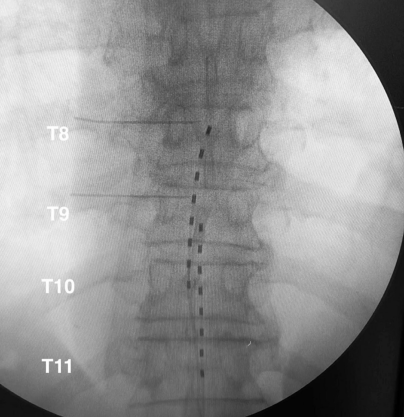

术前MRI显示,颈髓在C3-C6节段出现广泛的髓内T2高信号。由于之前椎板切除术区域存在纤维化瘢痕组织,SCS电极无法植入颈段硬膜外间隙,因此将2根电极植入T8-T11节段,并进行体外测试治疗。3周测试期间,患者疼痛明显改善,随后进行了永久植入。刺激参数为:频率10kHz,脉宽30μs,双极刺激,幅度范围0.5mA-3.5mA。